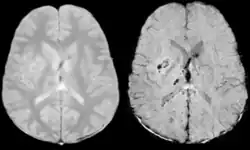

Comparison of diffuse axonal injury imaged with conventional GRE (left) and SWI (right) at 1.5 T

Comparison of hemorrhage imaged with conventional GRE (left) and SWI (right) at 1.5 T

The detection of micro-hemorrhages, shearing, and diffuse axonal injury (DAI) in trauma patients is often difficult as the injuries tend to be relatively small in size and can be easily missed by low resolution scans. SWI is usually run at relatively high resolution (1 mm3) and is extremely sensitive to bleeding in the gray matter/white matter boundaries making it is possible to see very small lesions increasing the ability to detect more subtle injuries.

Diffusion weighted imaging offers a powerful means to detect acute stroke. Although it is well known that gradient echo imaging can detect hemorrhage, it is best detected with SWI. In the example shown here, the gradient echo image shows the region of likely cytotoxic edema whereas the SW image shows the likely localization of the stroke and the vascular territory affected (data acquired at 1.5 T).

The bright region in the gradient echo weighted image shows the area affected in this acute stroke example. The arrows in the SWI image may show the tissue at risk that has been affected by the stroke (A, B, C) and the location of the stroke itself (D). The reason that we are able to see the affected vascular territory could be because there is a reduced level of oxygen saturation in this tissue, suggesting that the flow to this region of the brain could be reduced post stroke. Another possible explanation is that there is an increase in local venous blood volume. In either case, this image suggests that the tissue associated with this vascular territory could be tissue at risk. Future stroke research will involve comparisons of perfusion weighted imaging and SWI to learn more about local flow and oxygen saturation.